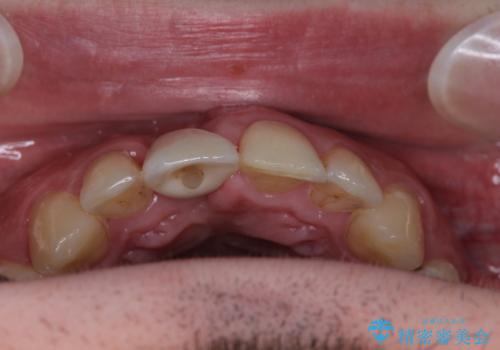

- 外れるたびに接着剤で応急処置を施してきた前歯のインプラント治療を希望して来院された患者様です。

以前から治療が必要であることは認識されていましたが、海外から日本に移住された1週間後に前歯が脱離したことで、当院でのインプラント治療を選択されました。

磨き残しなどによるプラークの付着が多いため、仮歯の用意と手術アポイントの調整を行っている間に口腔内のクリーニングなどを施し、環境がある程度改善されたのちに、抜歯即時インプラント埋入、即時荷重(インプラント埋入時に仮歯の装着)の予定で治療を行うこととしました。

度重なる脱離により、表側の炎症が非常に強くなっており、歯を支える骨が失われている状態でした。

そのため、現在の位置よりも歯と歯肉の位置が退縮する方向に移動する可能性があり、前歯2本の歯肉位置が大きくずれることとなるため、本人との相談のうえ、天然歯が萌えているような歯肉状態とはならないものの、2本の段差が少ない状態にて治療を終えることとなりました。